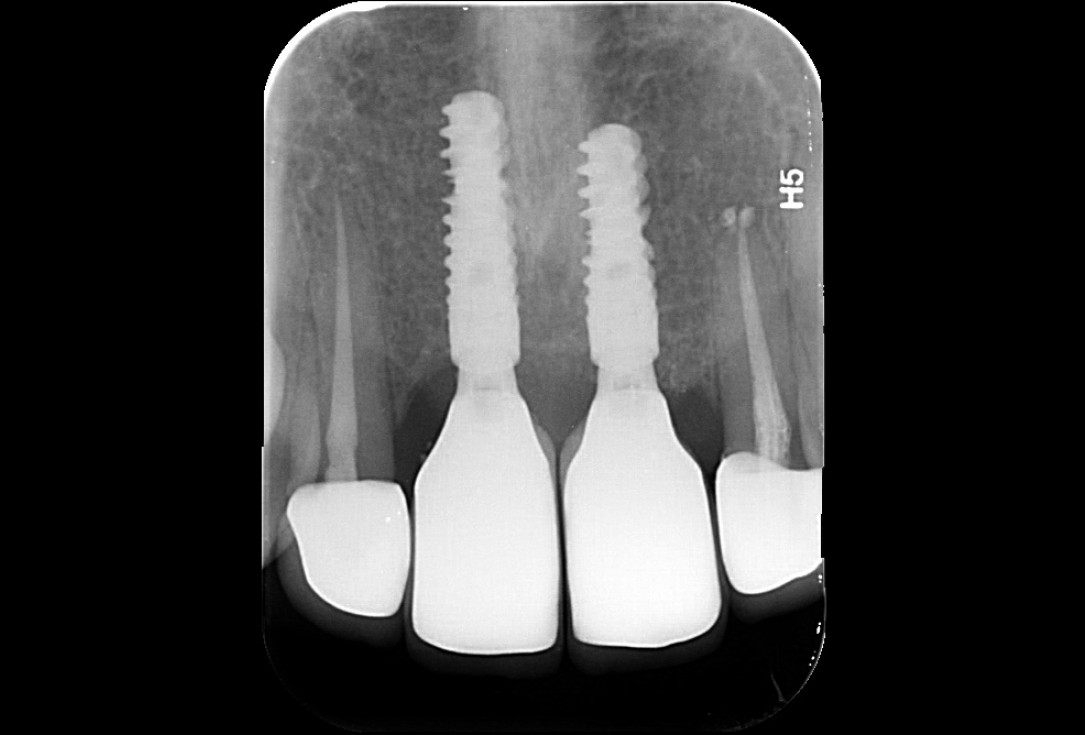

25/26 - X-ray scan at implant installation 6 months after augmentation

Ridge augmentation in the maxilla with maxgraft® bonebuilder in the aesthetic zone - Dr. M. Kristensen

26/26 - Final x-ray scan 12 months after augmentation